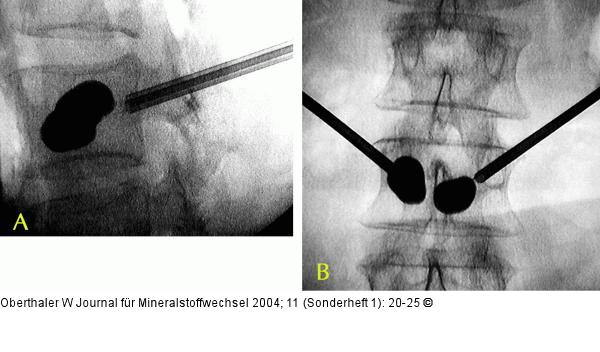

Abbildung 4a-b: Kyphoplastie Kyphoplastie: Durch den Ballon können Wirbel aufgerichtet und präformierte Hohlräume geschaffen werden |

Abbildung 4a-b: Kyphoplastie

Kyphoplastie: Durch den Ballon können Wirbel aufgerichtet und präformierte Hohlräume geschaffen werden |